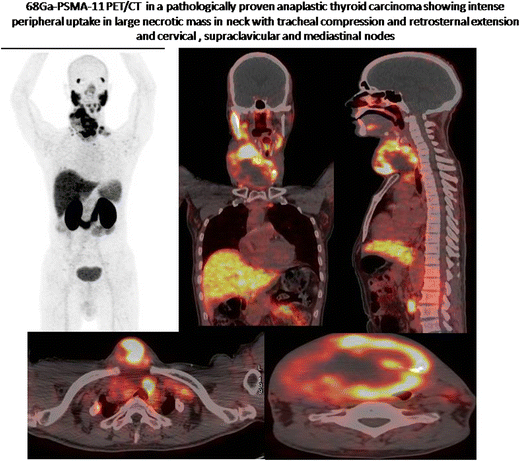

Prostate-Specific Membrane Antigen (PSMA) PET/CT has been extensively used in the management of patients with prostate cancer. This tracer also offers an important example of the concept of theranostics. However, PSMA expression has also been reported previously in other malignancies such as bladder, breast, gastric, colon, and lung cancers, as well as renal cell carcinoma, and in some non-neoplastic conditions [17]. Few studies have shown expression of PSMA in thyroid cancer [810]. To the best of our knowledge this is the first report of intense PSMA expression in anaplastic thyroid carcinoma (ATC). It is well known from some earlier studies that PSMA expression is seen in the endothelium of tumor neovasculature where there is abnormal protein expression and increased transcription of PSMA through activation of the transcriptional enhancer region in endothelial cells. PSMA expression may be seen in ATCs since they have very high vascularity. In this case, PSMA PET/CT showed high uptake in the primary tumor, cervical and mediastinal nodes (Fig. 1). The uptake was most intense in the periphery of the tumor concordant with the expected distribution of neovasculature. The patient also had multiple tiny nodules in bilateral lungs, but uptake was not discernible, possibly because of small size. This may open up a new possible therapeutic option for using 177 Lu-PSMA-DKFZ-617 therapy to treat ATC.